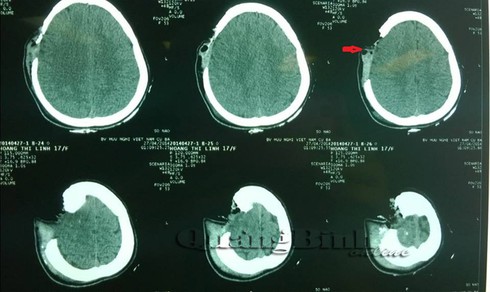

Sáng 28-4, tin từ Bệnh viện hữu nghị Việt Nam-Cu Ba Đồng Hới cho biết, sau 2 ngày cấp cứu, chăm sóc đặc biệt bệnh nhân nữ H.T.L (17 tuổi, ở xã Nam Trạch, huyện Bố Trạch), bị vỡ một mảng xương sọ kích thước khoảng 10cm x12cm đã qua cơn nguy kịch.

Xương sọ bệnh nhân L. bị khuyết một mảng (phim CTscaner). |

Trước đó, bệnh nhân L. do bị tai nạn giao thông gây chấn thương vào đầu nên một mảng xương sọ văng hẳn ra ngoài. Mảng xương sọ sau đó được người nhà gói trong tờ báo và đưa vào bệnh viện cùng với nạn nhân.

Sau khi được các bác sĩ thăm khám chẩn đoán, bệnh nhân được chuyển mổ cấp cứu cầm máu và xử trí vết thương, còn mảng xương sọ thì thì được làm sạch và cất giữ vào dưới da bụng chờ bệnh nhân ổn định thì lắp ghép vào sọ trở lại.